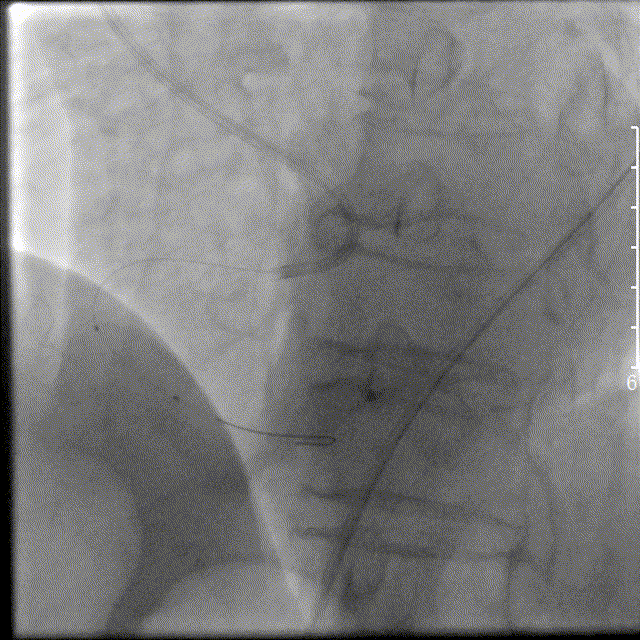

左图:选择6F SAL1.0指引导管,放至右冠状动脉开口,将Runthrough钢丝放至右冠状动脉远段。

右图:以博迈Artimes 2.0×20mm球囊对右冠状动脉中段病变进行扩张,造影见右冠状动脉血流恢复,血流缓慢,可见血栓影。